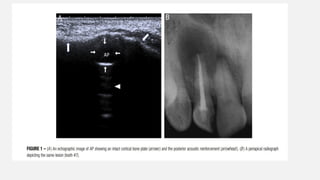

Figure 1 (A-C):Periapical cyst. A) Intraoral periapical radiograph shows a well-circumscribed radiolucent periapical lesion (arrow) with a partial sclerotic border, measuring more than 1 cm in diameter. B) USG with color Doppler and power Doppler shows a hypoechoic,well- contoured cavity (arrow) with no evidence of internal vasculature on color and power Doppler examinations. C)H and E stained section shows the presence of an epithelial lining (arrow) with underlying dense fibrocellular connective tissue stroma

• 76.

Figure 2 (A-C):Periapical granuloma. A)Intraoral periapical radiograph shows a well-circumscribed radiolucent periapical lesion (arrow) without a sclerotic border, measuring less than 1 cm in size. B)USG with color Doppler and power Doppler shows a poorly defined hypoechoic lesion (arrow) exhibiting a rich vascular supply on color and power Doppler examinations. C)H&E stained section shows fibrocellular connective tissue stroma (arrow) consisting of chronic inflammatory cell infiltrate and endothelium-lined blood capillaries with red blood cells, fibroblasts, and collagen fibers

• 77.

o The difference betweenthe accuracy of radiographs and USG for the detection of periapical cyst and periapical granuloma proved to be highly significant ( P<0.001) USG with color Doppler and power Doppler is superior to conventional intraoral radiographic methods for diagnosing the nature of periapical lesions in the anterior jaws.